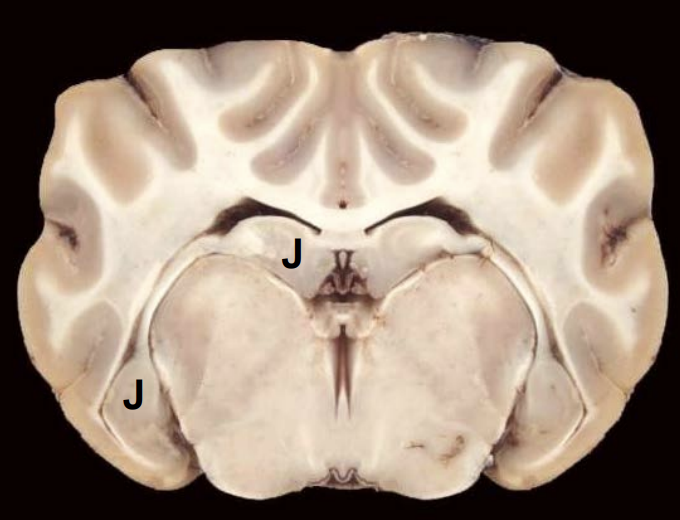

Q

J

A

Hippocampus